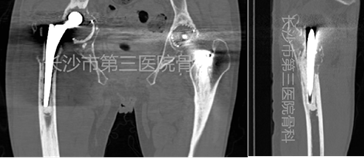

二期翻修术前CT

长沙市第三医院骨科雷青主任医师认为患者诊断右侧髋关节假体周围感染明确,具备手术指征及条件,联合本院3D打印工作室团队合作,设计二期翻修术前定制3D打印抗生素骨水泥临时假体印模,以解决上述徒手制作抗生素骨水泥临时假体中存在的问题,并减少手术时间及风险。